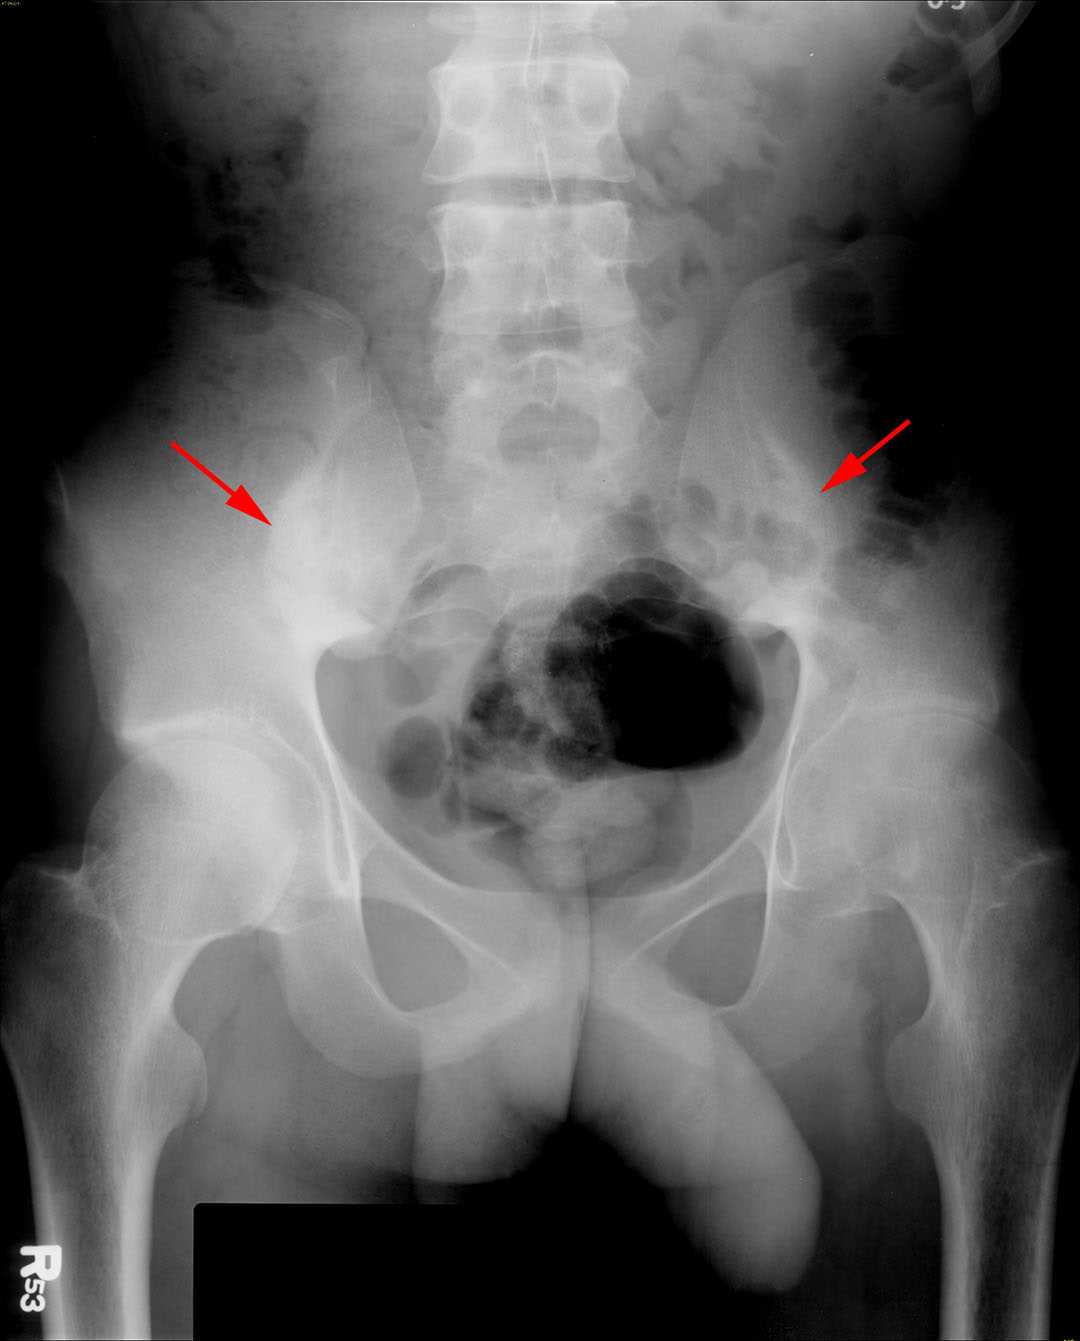

Ankylosing Spondylitis Pelvis X Ray Ankylosing Spondylitis X Ray Si Joint Ankylosing spondylitis often affects the sacroiliac or si joint, which may cause pain in the lower back or buttocks. Early changes of sacroiliitis (inflammation of the sacroiliac joints) are not. Imaging is an integral part of the management of patients with ankylosing spondylitis and axial spondyloarthritis. It typically affects your sacroiliac joint, where your spine and pelvis meet. Dosing informationwatch. Ankylosing Spondylitis X Ray Si Joint.

Ankylosing spondylitis. Anteroposterior radiograph of sacrum shows Ankylosing Spondylitis X Ray Si Joint Ankylosing spondylitis is a chronic seronegative autoimmune spondyloarthropathy characterized by bridging spinal osteophyte formation, enthesitis, sacroiliitis,. Ankylosing spondylitis (as) is a chronic, inflammatory disease primarily affecting the axial spine that can manifest with a range of clinical signs and symptoms. Ankylosing spondylitis is a type of arthritis that causes pain and stiffness in your spine and other joints. Imaging is. Ankylosing Spondylitis X Ray Si Joint.

ANKYLOSING SPONDYLITIS, XRAY Stock Photo 66575768 Alamy Ankylosing Spondylitis X Ray Si Joint Early changes of sacroiliitis (inflammation of the sacroiliac joints) are not. Dosing informationwatch videos for hcps Ankylosing spondylitis is a chronic seronegative autoimmune spondyloarthropathy characterized by bridging spinal osteophyte formation, enthesitis, sacroiliitis,. Ankylosing spondylitis (as) is a chronic, inflammatory disease primarily affecting the axial spine that can manifest with a range of clinical signs and symptoms. Ankylosing spondylitis most commonly. Ankylosing Spondylitis X Ray Si Joint.